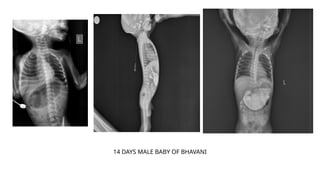

USG showing whirlpool sign of vessels which confirms

the presence of volvulus

14 DAYS MALE BABY OF BHAVANI

USG showing whirlpoolsign of vessels which confirms the presence of volvulus

14 DAYS MALEBABY OF BHAVANI